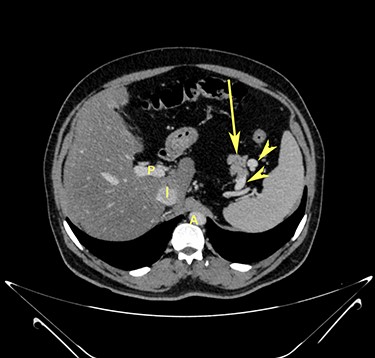

Transverse section image of a contrast-enhanced CT scan of the abdomen at level 1–1 (Fig. 1), showing the pancreas’ normal tail (long arrow). Splenic vessels are labelled using arrowheads.